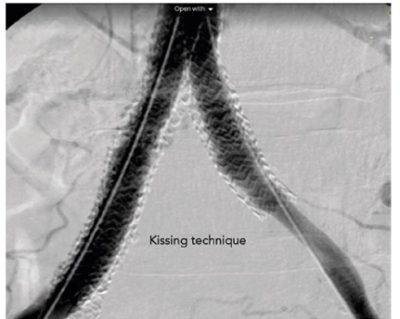

ثانيا: “الدعامه الطرفيه ذات الفتح بالبالون”

– تعتمد هذه الدعامه علي استخدام البالون للفتح

– تستخدم للانسدادت العنيفه ولكن القصيره في الشريان الحرقفي (الحوض)

– من مميزاتها الدقه المتناهيه في الأداء ، قوه الدعامه في التغلب علي الانسداد ، يتم التوسيع الشرياني بالبالون ووضع الدعامه في ان واحد